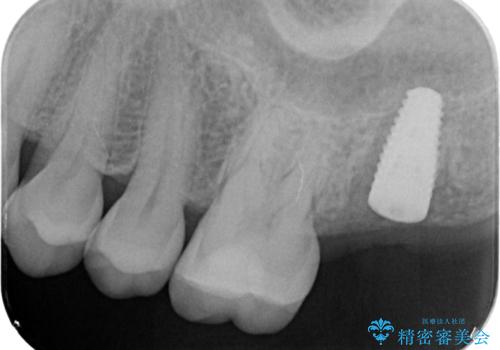

精査した結果、上顎奥歯は歯が割れてしまっており、根管治療ではなく抜歯の対象でした。

歯の抜去後、しっかりと咬合機能を回復するためインプラントを用いた治療を行っていきます。

- 50.4万円(インプラント・チタンカスタムアバットメント・ジルコニアクラウン・仮歯)費用は治療当時の料金となります